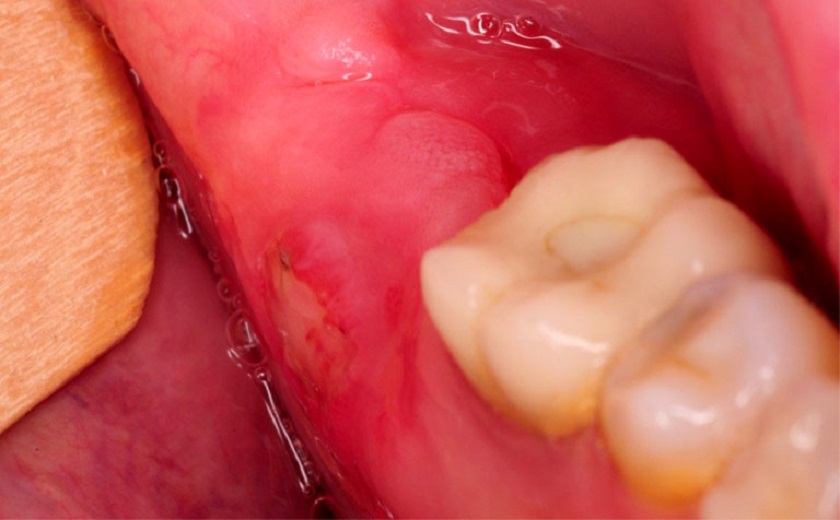

Đa số răng khôn khi mọc lên đều gây đau nhức và sưng nướu. Tuy nhiên, nếu răng khôn mọc đúng hướng thì cảm giác đau sẽ chấm dứt hoàn toàn khi quá trình mọc kết thúc. Thời gian răng mọc hết có thể kéo dài từ vài tháng đến vài năm. Đối với những người có răng mọc ngầm, mọc lệch thì sẽ dẫn đến hiện tượng sưng đỏ, viêm nhiễm, có mủ và cơn đau sẽ nặng nề hơn rất nhiều. Lúc này, bạn nên nhổ bỏ chúng để ngăn ngừa các biến chứng về sau.

Răng khôn gây sưng viêm nướu